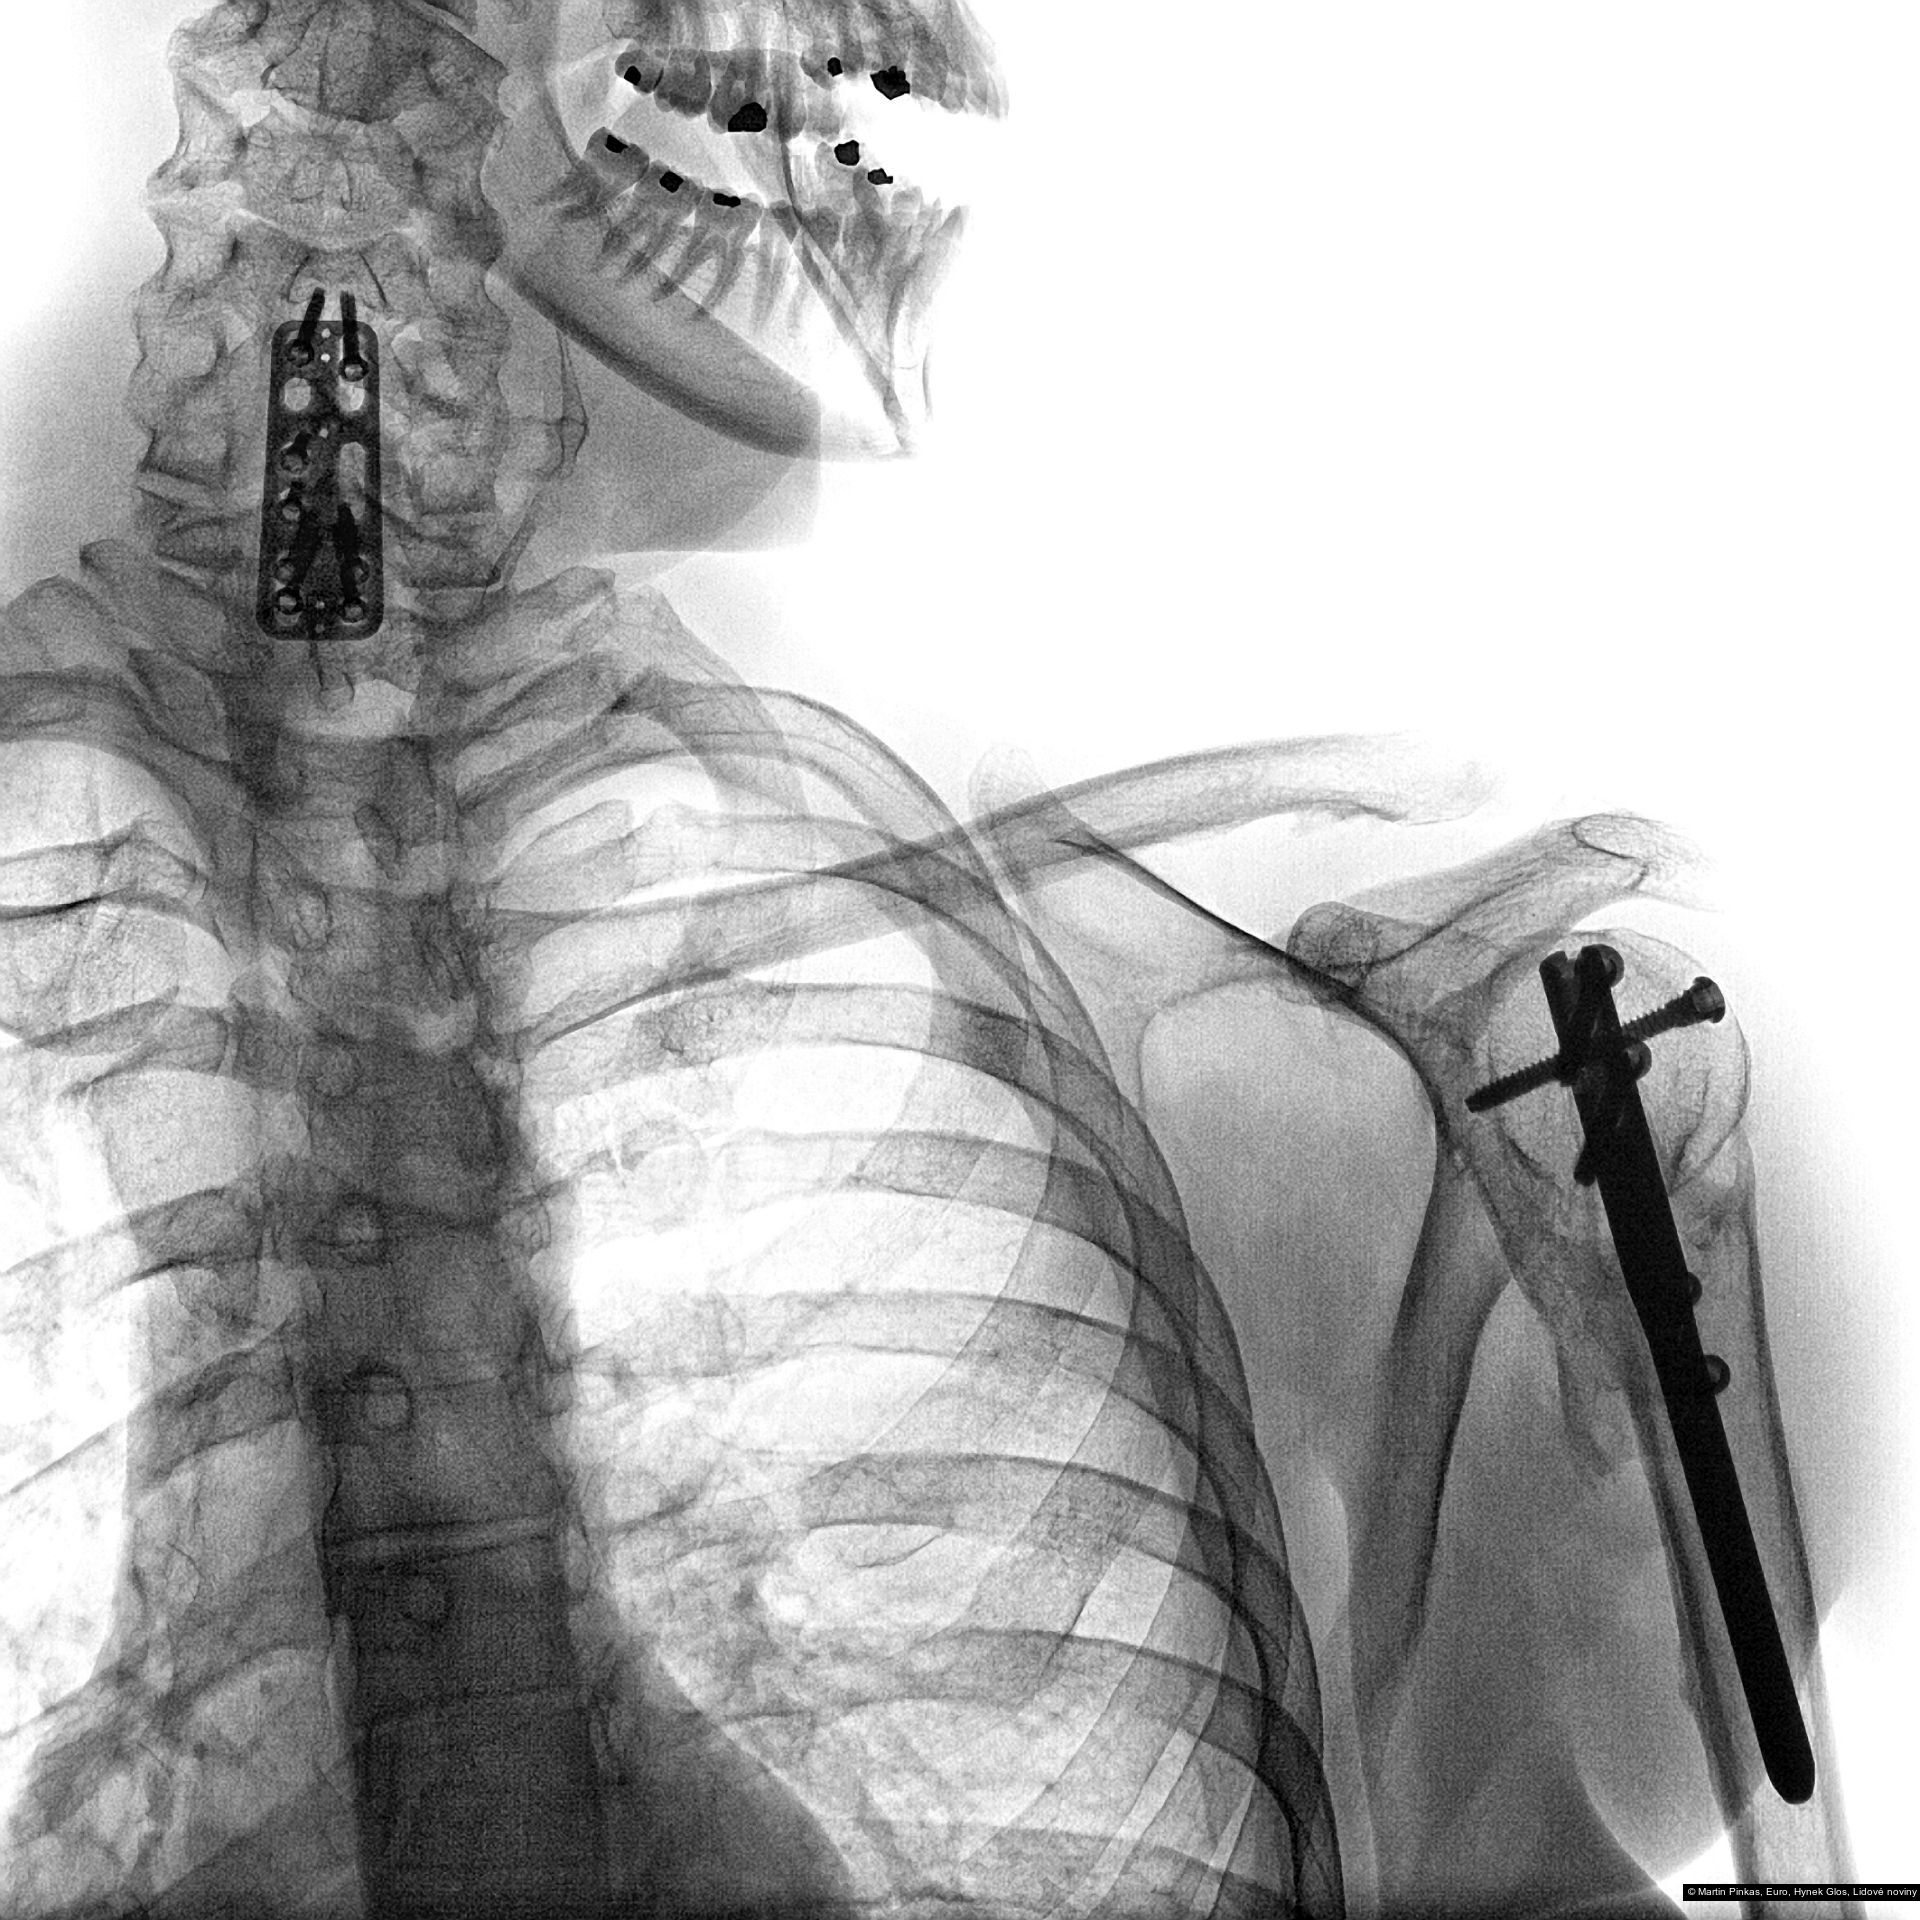

Příspěvek: X-portrait, nelékařské rentgenové portréty handicapovaných sportovců, Praha, Mostiště, 6.8. - 15.9.2010

Autor: Hynek Glos, Martin Pinkas

Příspěvek: X-portrait, nelékařské rentgenové portréty handicapovaných sportovců, Praha, Mostiště, 6.8. - 15.9.2010

Autor: Hynek Glos, Martin Pinkas

Příspěvek: X-portrait, nelékařské rentgenové portréty handicapovaných sportovců, Praha, Mostiště, 6.8. - 15.9.2010

Autor: Hynek Glos, Martin Pinkas

Příspěvek: X-portrait, nelékařské rentgenové portréty handicapovaných sportovců, Praha, Mostiště, 6.8. - 15.9.2010

Autor: Hynek Glos, Martin Pinkas

Příspěvek: X-portrait, nelékařské rentgenové portréty handicapovaných sportovců, Praha, Mostiště, 6.8. - 15.9.2010

Autor: Hynek Glos, Martin Pinkas

Příspěvek: X-portrait, nelékařské rentgenové portréty handicapovaných sportovců, Praha, Mostiště, 6.8. - 15.9.2010

Autor: Hynek Glos, Martin Pinkas

Příspěvek: X-portrait, nelékařské rentgenové portréty handicapovaných sportovců, Praha, Mostiště, 6.8. - 15.9.2010

Autor: Hynek Glos, Martin Pinkas

Příspěvek: X-portrait, nelékařské rentgenové portréty handicapovaných sportovců, Praha, Mostiště, 6.8. - 15.9.2010

Autor: Hynek Glos, Martin Pinkas

Příspěvek: X-portrait, nelékařské rentgenové portréty handicapovaných sportovců, Praha, Mostiště, 6.8. - 15.9.2010

Autor: Hynek Glos, Martin Pinkas